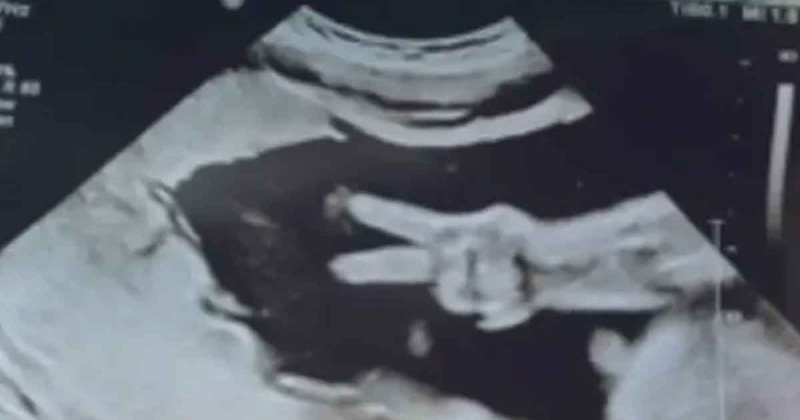

Bebé sorprende a sus padres al hacer la señal de amor y paz en ecografía

Una pareja tuvo un día lleno de amor y ternura luego de que acudieron a un estudio de rutina, pero quedaron llenos de asombro cuando su bebé hizo la señal de amor y paz